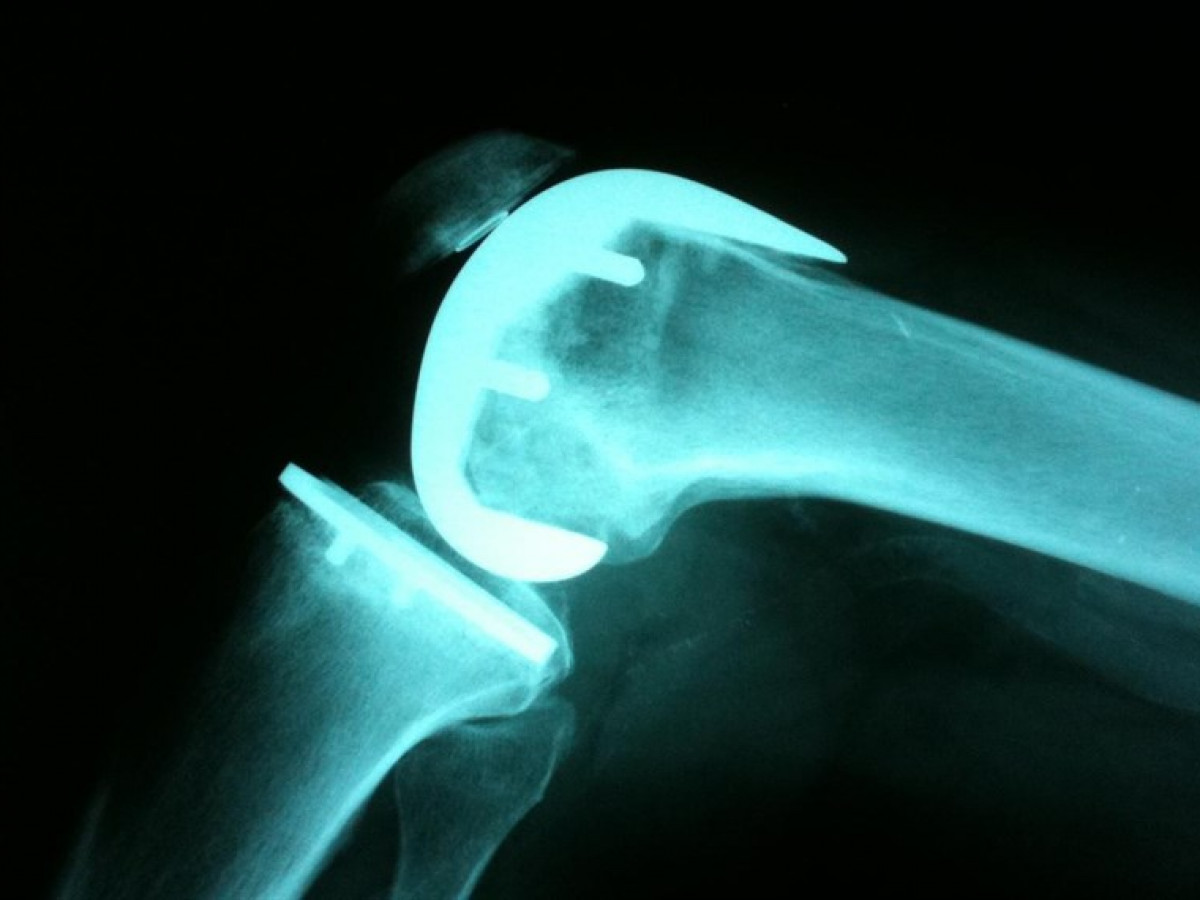

La Inteligencia Artificial ya analiza radiografías en el SERGAS en Santiago, Ferrol y O Barbanza